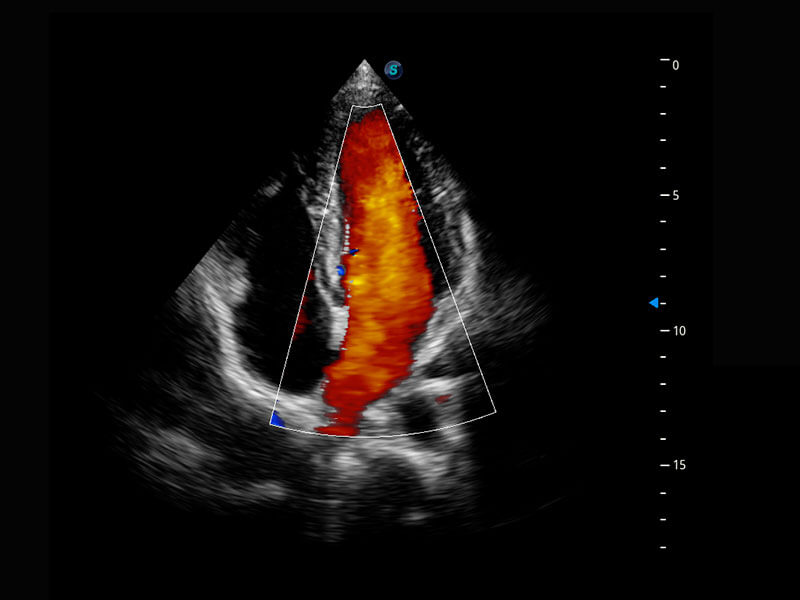

早孕筛查

P60在胎儿早孕期超声筛查中为您带来优异的图像质量。

• 胎儿体循环